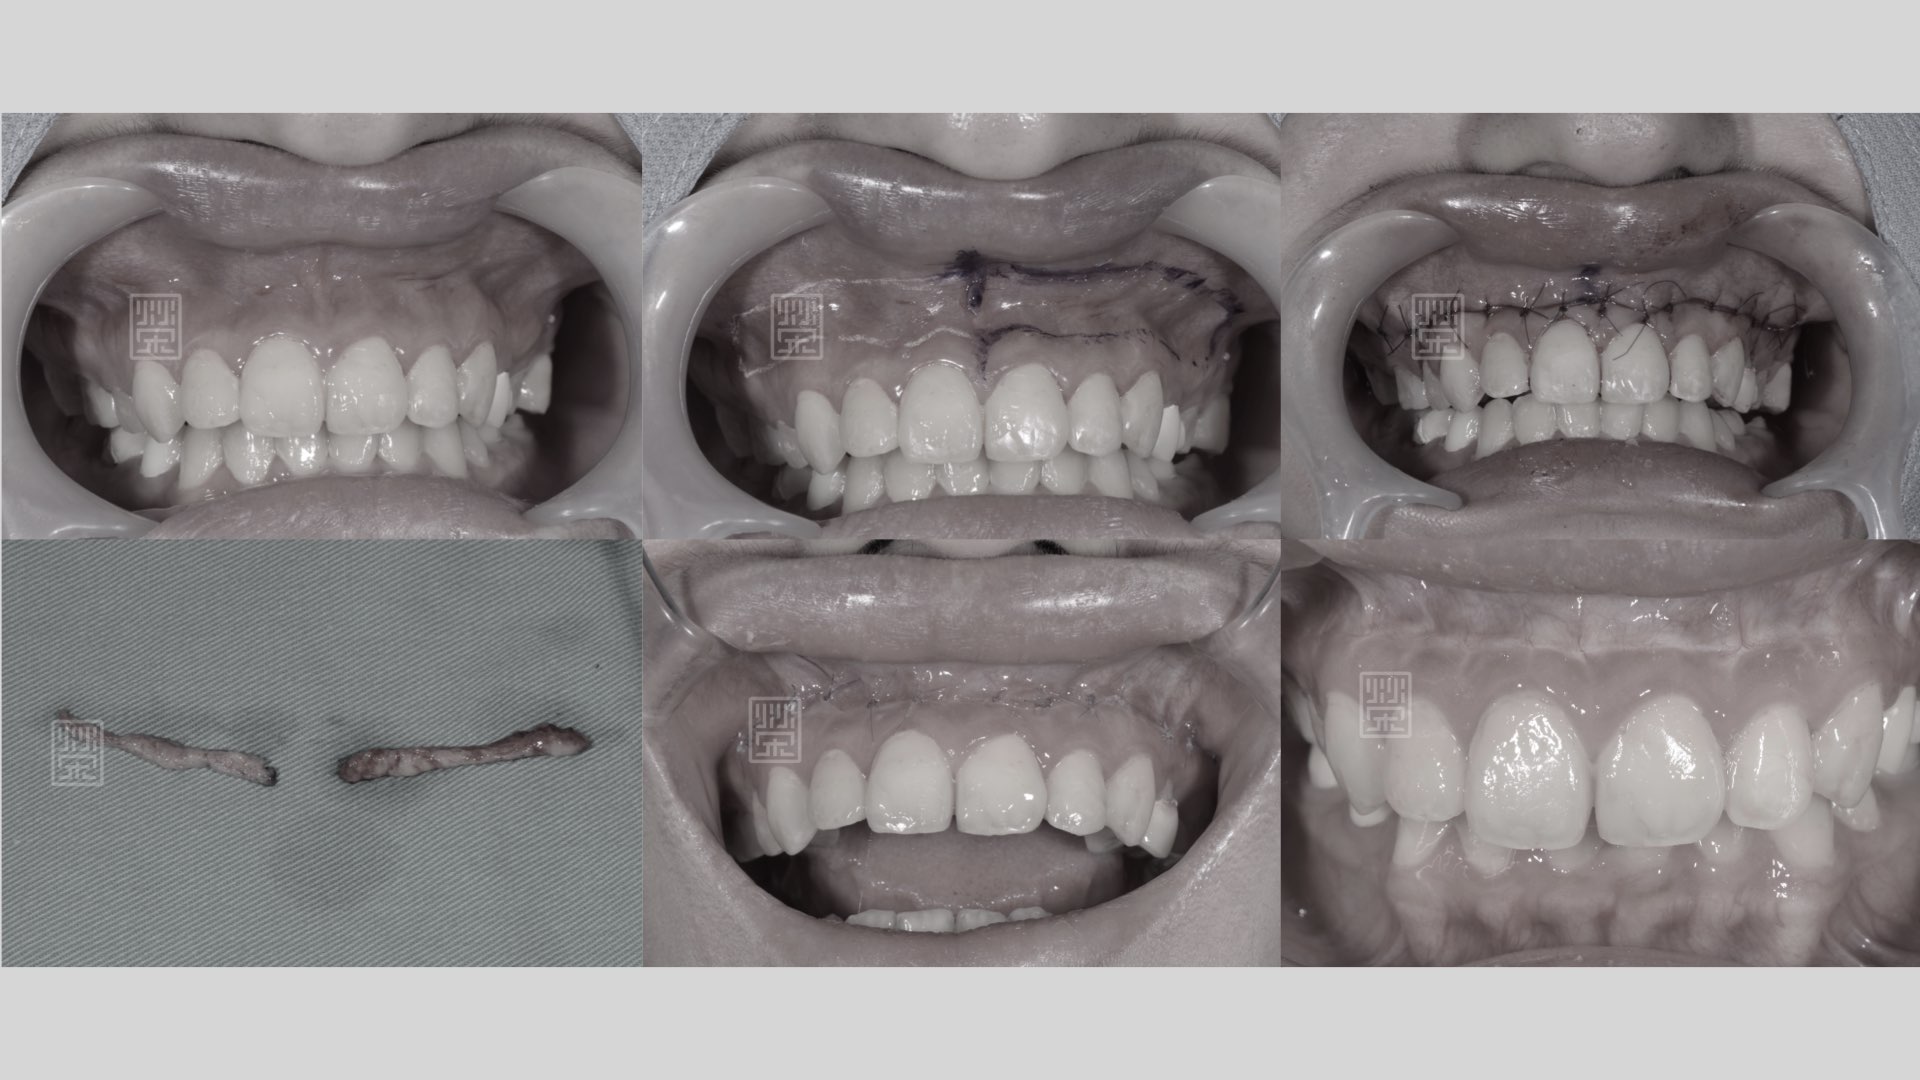

除此之外,陳小姐笑起來的時候,牙齦露出來很多,在開懷大笑時,有點困擾,榮醫師分析後,發現他的牙齒比例位置是蠻正確的,所以用上唇重置術(lip reposition),改善陳小姐笑齦的問題。

笑齦改善

上唇重置術

笑齦明顯、尺色偏黃